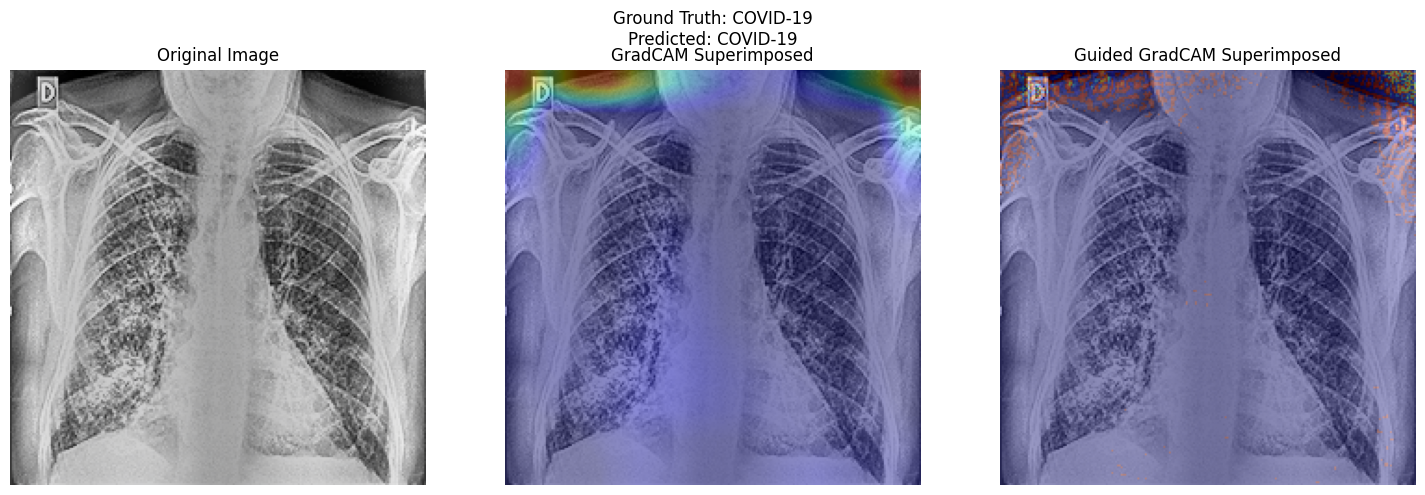

• Comparing Original Image with Grad Cam and Guided Grad Cam Heatmap Superimposed Image respectively.

Activation Map Visualisation

Research Question 2 and Model Interpretability.

• Research Question 2 : What insights can be derived from activation visualization or attention map visualization about the decision-making process of the pre-trained vgg19, resnet50 models or custom CNN and vision transformer models, respectively, in predicting respiratory diseases from chest radiological images?

• Insights from Activation and Attention Map Visualizations in Chest Radiological Images Classification

• Activation and attention map visualizations offer transparency into neural networks, highlighting areas deemed significant during predictions. Such insights are crucial for medical imaging applications, where the understanding of a model's focus can aid in validation and trust.

• 1. ResNet50:

Using gradient-based visualization, ResNet50 pinpoints distinct chest X-ray features indicative of respiratory diseases, like opacities. However, its attention sometimes extends to noise and image edges. This could be influenced by the zoom preprocessing, emphasizing both critical regions and noise.